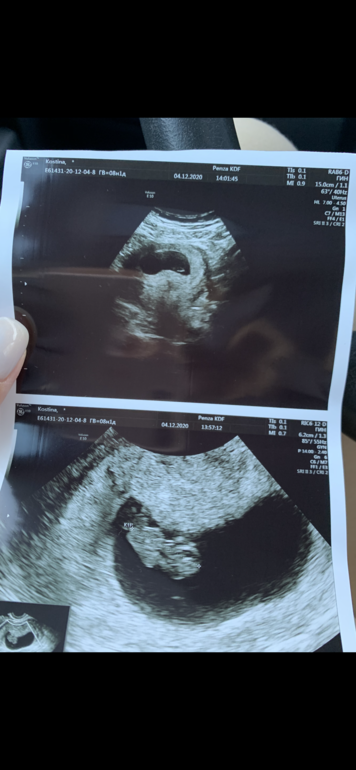

8 нед 1 день узи, по рамзи пол не определить?

Моя мазня и 🩸, является нормой, ни гематом, ни отслоек тьфу тьфу тьфу не появилось, все сказал хорошо, растем точно в срок... Мазня сейчас сказал может быть из-за того что плодное яйцо растет и вытесняет ненужный ему эндометрий, с обратной стороны, да и расположение низкое к шейке, но пока это не результативно, когда плацента сформируется скорей всего поднимется.

Сделал мне наши первую фотку ❤️

Итак итак делали, честно не помню какие фотки по животу какие вагинально, все как в тумане